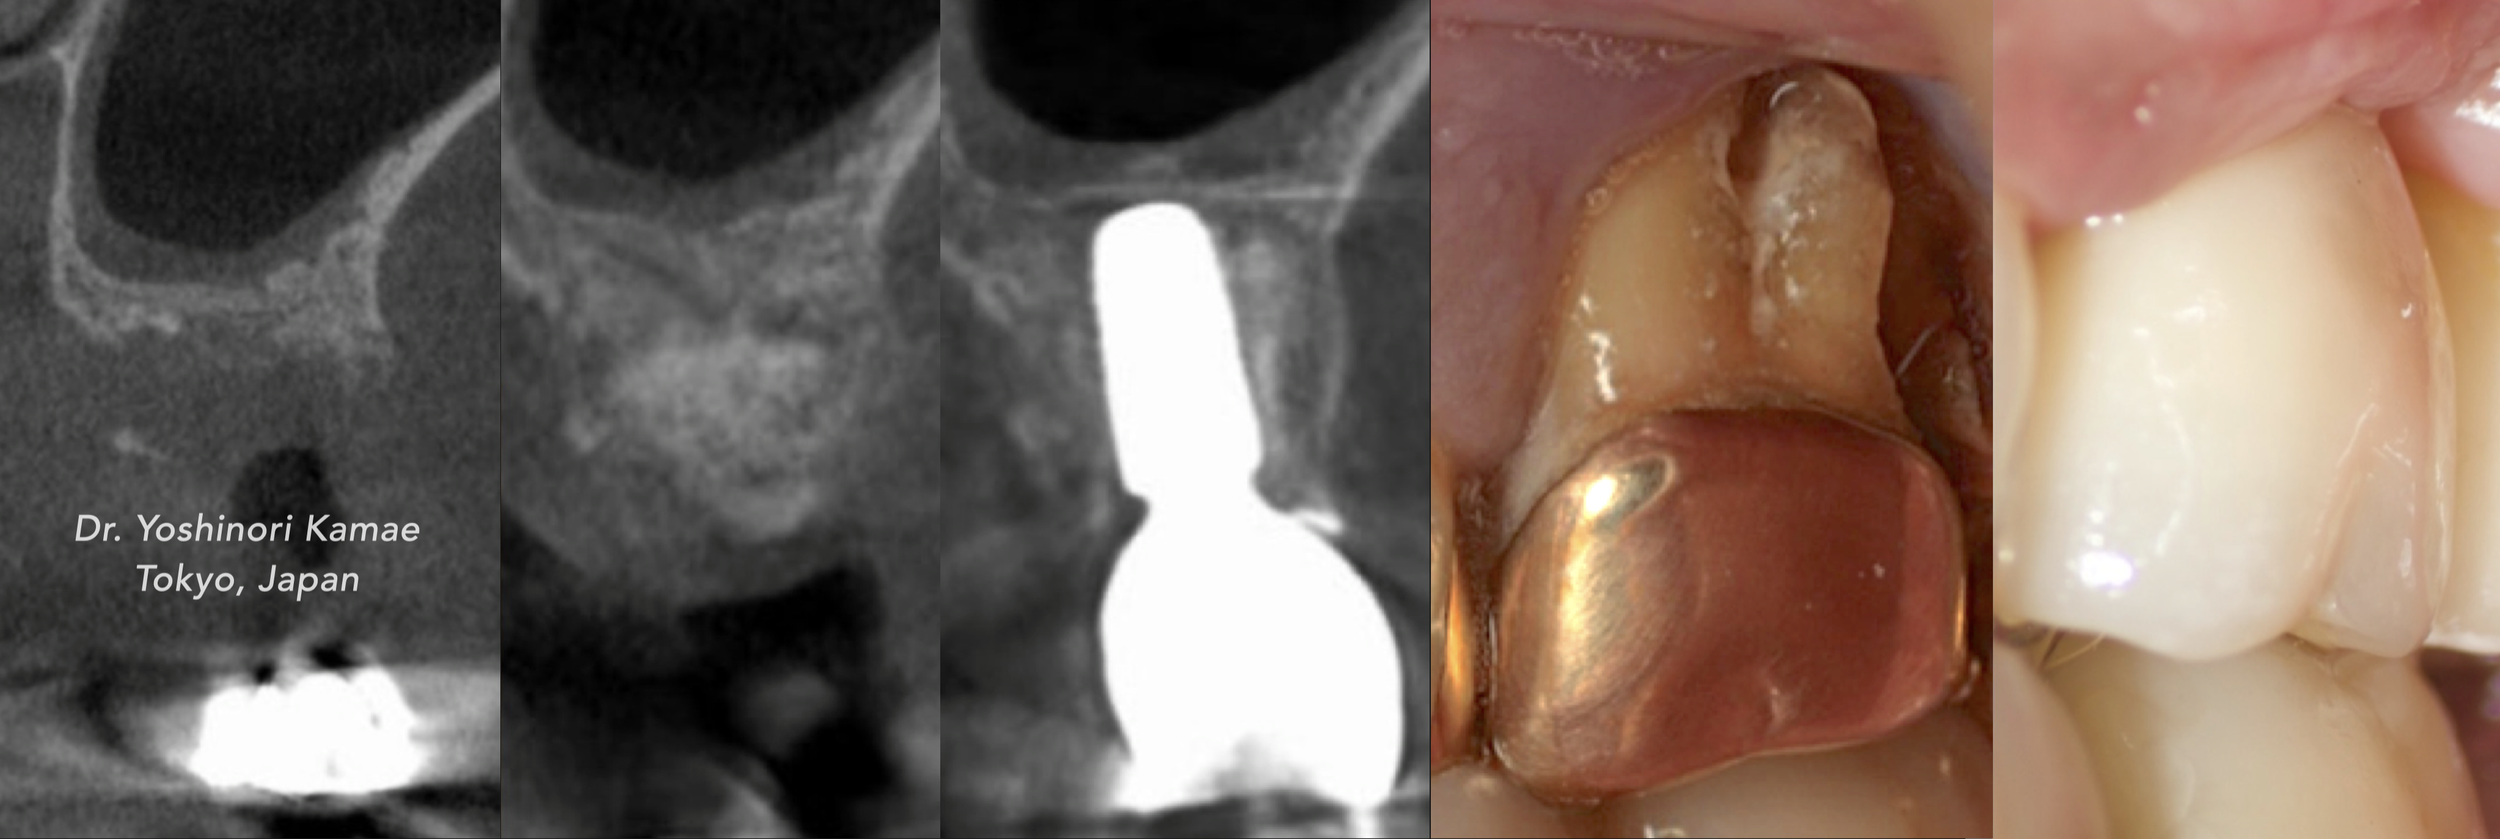

Clinical Cases CASE 1. COMPLEX IATROGENIC DEFECT CASE 2. CONGENITALLY MISSING LATERAL INCISORS CASE 3. VERTICAL AUGMENTATION CASE 4. VERTICAL AUGMENTATION CASE 5. IMPLANT BONE DEHISCENCE CASE 6. IMPLANT BONE DEHISCENCE CASE 7. KNIFE-EDGE RIDGE CASE 8. IMMEDIATE IMPLANT AND SIMULTANEOUS S.M.A.R.T.® HORIZONTAL AUGMENTATION CASE 9. IMMEDIATE IMPLANT AND SIMULTANEOUS S.M.A.R.T.® HORIZONTAL AUGMENTATION